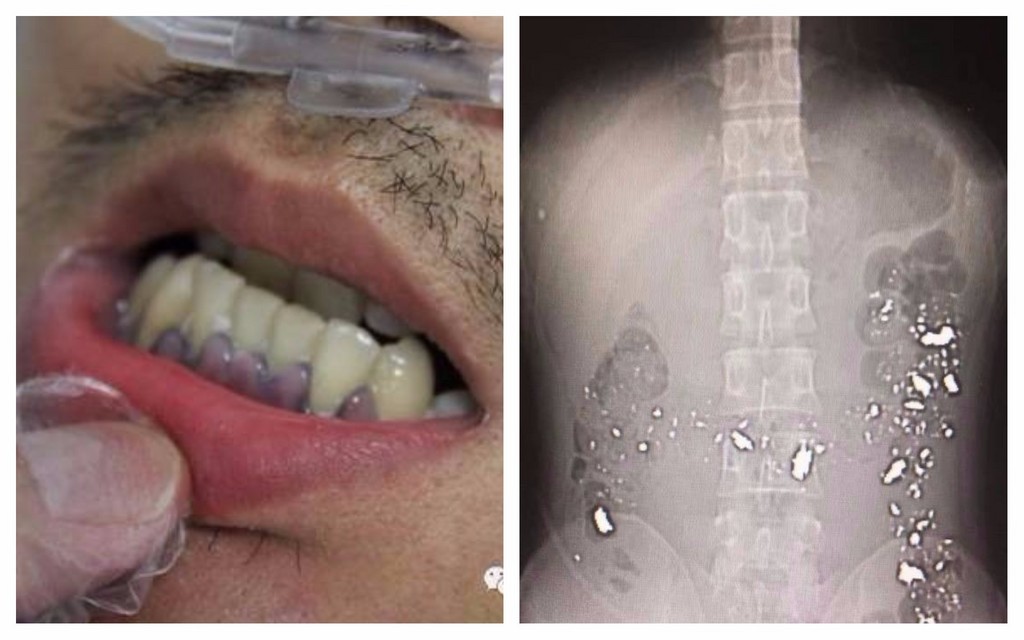

▲患有精神疾病的男子深信煉丹術,吞鉛粉搞到滿肚子「金光閃閃」。(圖/翻攝自台州市中心醫院微博,下同)

浙江省台州市一家醫院15日有名蔡姓年輕人求診,男子只是反復說「頭痛、噁心」但其餘症狀不得而知,經檢查頭部也無恙,但在X光檢查腹部後,才發現男子一肚子都是閃閃發光的金屬,院方詢問後才知道,這名年輕人原來已經食鉛1年時間。

急症重症監護專家吳立群說,該患者的造血功能已經受到相當嚴重的損害,就連他的肝臟也因此受損,且由於患者長期食鉛,他的牙齦上還能看到明顯的鉛線。

據報導,院方安排蔡男住院後,對他進行驅鉛治療,以盡量減少已被吸收的鉛對人體產生危害,並同時進行導瀉治療,盡快將患者腸胃理的鉛粉排出去;此外,經檢查患者確診為精神分裂症,在驅鉛治療的同時,也會針對精神疾病進行治療。